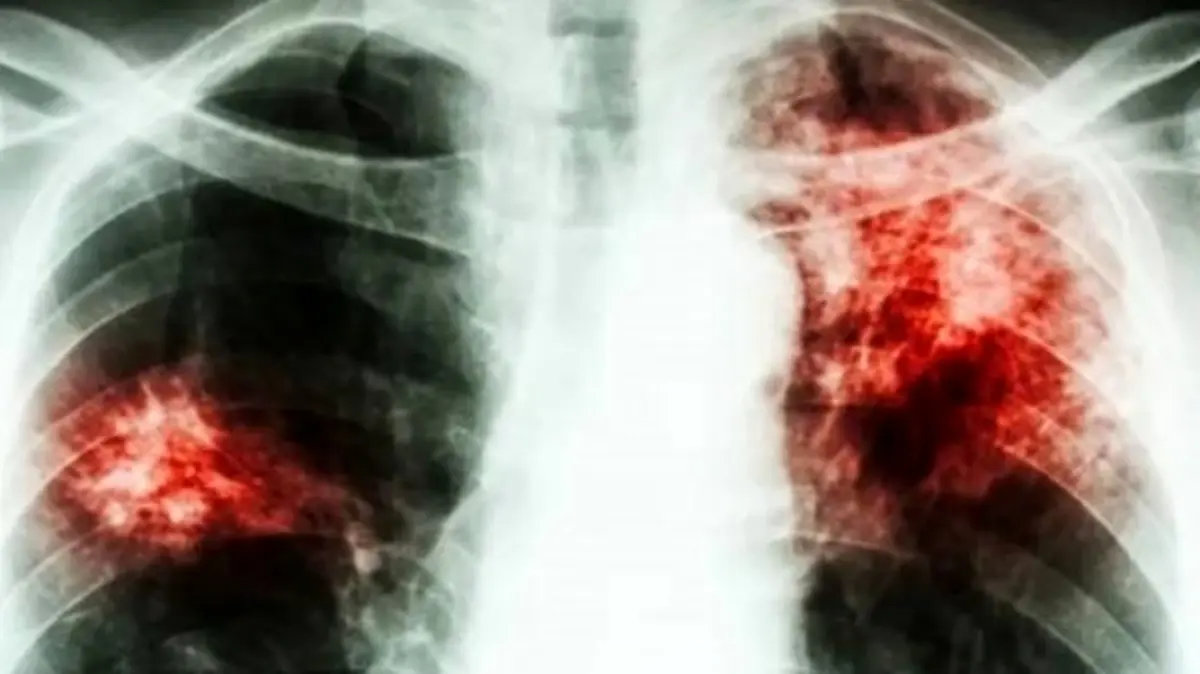

به گزارش رکنا، سل یکی از بیماریهای عفونی و واگیر است که به واسطهی میکروبی به نام باسیل سل ایجاد میشود. این بیماری قابلیت آلوده کردن قسمتهای مختلفی از بدن نظیر استخوانها، مفاصل، مغز، کلیه و پوست را دارد؛ اما میزان اکسیژن بالا در ریهها باعث میشود در ۸۰ درصد موارد، هدف اصلی این بیماری قرار گیرد.

علائم سل ریوی شامل سرفه مداوم که ممکن است خلط داشته باشد یا نداشته باشد، تب عصرگاهی، کاهش وزن، عرق شبانه، بیاشتهایی، خستگی و ضعف عمومی است. در موارد پیشرفته، درد قفسه سینه، تنگی نفس و خلط خونی نیز مشاهده میشود. در صورت مشاهده این علائم، مراجعه فوری به پزشک ضروری است.

تهیه نمونه خلط و انجام آزمایش یکی از بهترین روشهای شناسایی بیماری سل است. در برخی موارد عکسبرداری از قفسه سینه یا آزمایشات تکمیلی نیز قابل انجام است. خدمات تشخیصی و درمانی این بیماری به صورت رایگان در مراکز بهداشتی کشور ارائه میشوند.